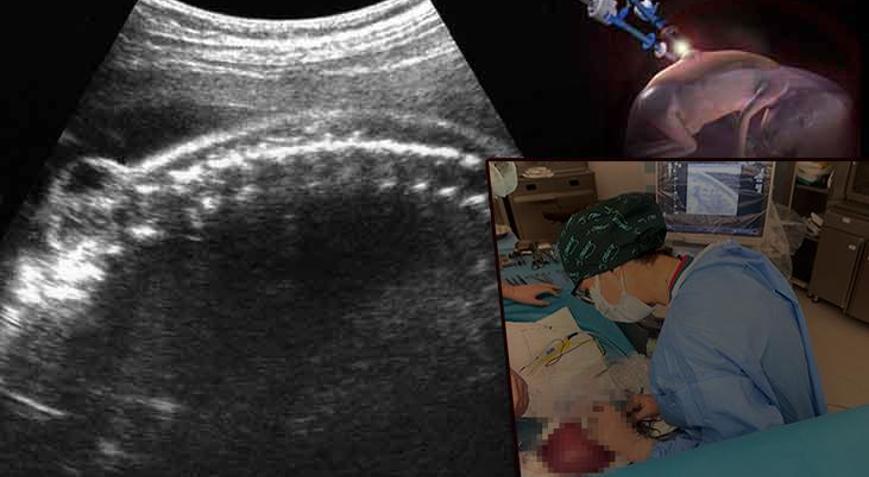

Hamileliğin ilk haftalarından itibaren düzenli olarak doktor kontrollerine giden Hatice Yıldırım, her seferinde bebeğinin sağlıklı olduğunu öğrenerek rahat bir nefes alıyordu. Ancak gebeliğin 22’nci haftasında yapılan detaylı ultrason taramasında her şey değişti. Yıldırım çiftine, bebeklerine 'spina bifida' tanısı konuldu. Ne kendi ailesinde ne de eşinin ailesinde daha önce böyle bir durum yaşanmıştı. Hatta Hatice Yıldırım, bu hastalığın adını ilk kez duyuyordu.

'NEDENİ KESİN OLARAK BİLİNEMİYOR'

Prof. Dr. Esra Esim Büyükbayrak hastalığın teşhisiyle ilgili, "Gebelik takipleri sırasında kadın hastalıkları ve doğum uzmanları tarafından yapılan ultrasonografik muayenelerle gebeliğin erken dönemlerinden itibaren tanısı konulabilir. Ultrasonografiyle bebeğin omurgasındaki açıklığın ve eğer varsa buradaki kese (myelosel) varlığının görülmesi tanı koydurucudur. Ayrıca omurgadaki açıklığa bağlı olarak kafa içi yapılarında gelişen bazı bulgular da (beyincik fıtıklaşması, kafa içinde sıvı toplanması (hidrosefali) ultrasonografiyle fark edilebilir ve tanı konulmasını kolaylaştırabilir. Ancak ‘spina bifida okulta’ olarak adlandırılan omurgadaki çok küçük açıklıklar bazen ultrasonografiyle saptanamayabilir" dedi.

Spina bifida için fetal cerrahi günümüzde üç teknikle yapılıyor. Bunlardan ilki, histerotomi ile açık fetal cerrahi olarak adlandırılıyor. Rahim sezaryen ameliyatındaki gibi dışarı alınıp rahime kesi yapılarak bebeğe ulaşılıyor. İkincisi fetoskopi ile kapalı fetal cerrahi. Rahim dışarı alınmadan fetoskopi aletleri annenin cildinden direkt rahim içine yerleştirilerek gerçekleştiriliyor. Bir de laparatomi asiste fetoskopik cerrahi adıyla bilinin hibrid yöntem bulunuyor. Burada da rahim açık ameliyattaki gibi dışarı alınıyor ancak rahme kesi atılmadan fetoskopi aletleri rahim içine yerleştirilerek ameliyat yapılıyor. Prof. Dr. Büyükbayrak, histerotomi ile açık fetal cerrahi yapılan hastaların rahimde bir kesi ve dikişler olduğu için sadece sezaryen yöntemiyle bebeklerini dünyaya getirebildikleri ancak laparatomi asiste fetoskopik cerrahi (hibrid yöntem) ve fetoskopi ile kapalı fetal cerrahi yapılan hastaların yaklaşık yüzde 75’inin sezaryenla doğum yaptığını, yüzde 25’inin de vajinal yolla doğurabildiğinin altını çizdi.